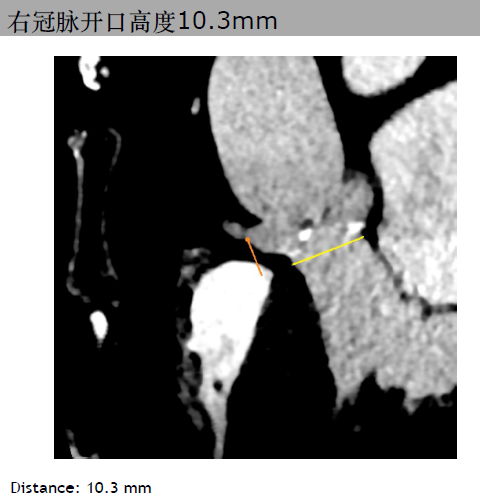

三叶瓣,主动脉瓣环平均直径21.3mm。右冠脉高度10.3mm,右窦直径:28.4mm。左冠脉高度14.1mm,左窦直径:30.4mm。STJ平均直径25.4mm,高度17mm。